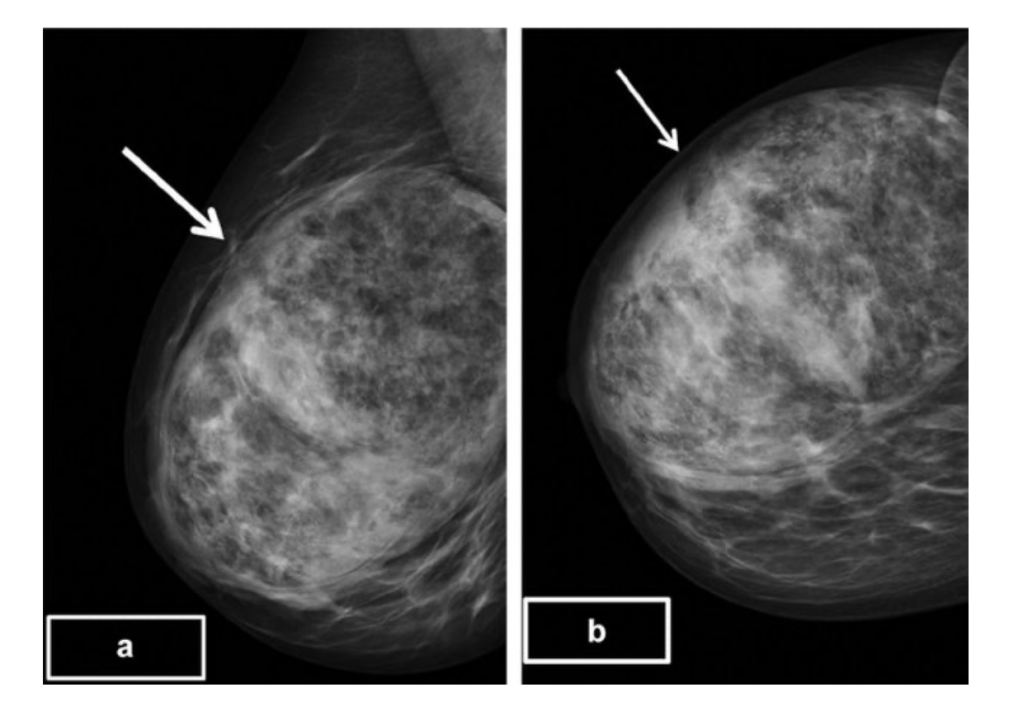

(a) and (b) – Digital mammograms, medio-lateral oblique (MLO) and cranio-caudad (CC) projections of the right breast showing an large ovoid, encapsulated mass lesion with a ‘breast ] within a breast’ appearance.